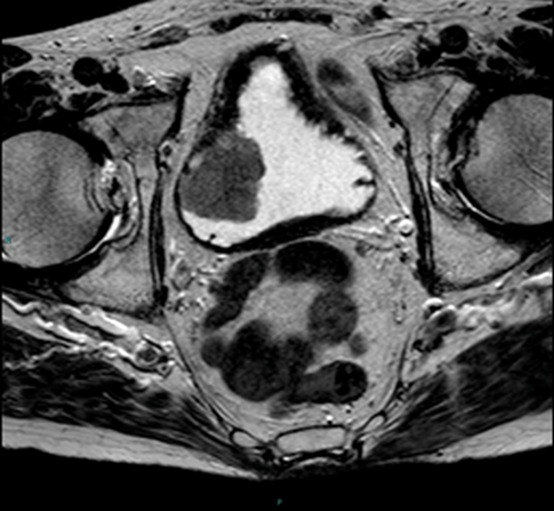

⬅️صورة الرنين المغناطيسي (MRI)

📌تصوير بالرنين المغناطيسي MRI